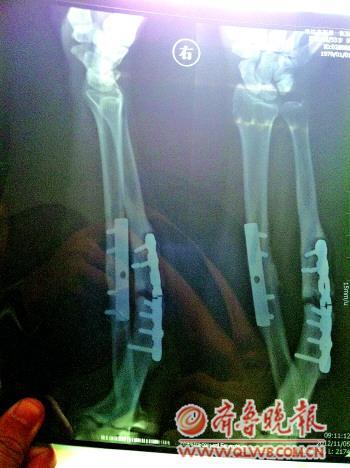

周波在尊一医院复查时拍的CT。周波的复诊报告单。文/片 本报记者 李小凯

周波拿着日前在3家医院做的检查结果给记者看。CT片子显示,周波右手前臂内有两块钢板,其中一块已经断裂,相应部位的骨头也有明显的断裂。周波说,前一阵子在家提水的时候,突然听到里面钢板发出“嘎嘣”一声,担心曾经骨折的前臂再出现问题,他和家人前往附近的医院做了CT,随后又前往尊一医院和潍坊市的另一家医院做了检查。

16日上午,尊一医院出具了周波的复查X线诊断报告单。报告单指出,周波右尺桡骨近端骨折钢板内固定术后复查,桡骨骨折基本愈合,尺骨固定钢板断裂,远端第二螺钉断裂,骨折线较宽,骨折端圆滑,其他未见异常。院方坚称当年的手术没有任何问题。从当年周波的治疗档案来看,周波出院前也签了《手术知情同意书》。